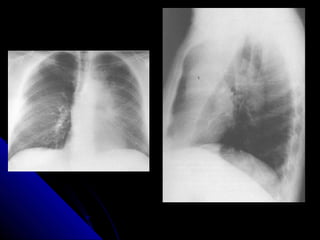

PPlleeuurraall eeffffuussiioonn

AA pplleeuurraall eeffffuussiioonn iiss ssiimmppllyy aa ccoolllleeccttiioonn ooff fflluuiidd

bbeettwweeeenn tthhee vviisscceerraall pplleeuurraa aanndd tthhee ppaarriieettaall

pplleeuurraa.. TThhiiss fflluuiidd ccoolllleeccttiioonn mmaayy bbee sseerroouuss

((pplleeuurraall eeffffuussiioonn)),, bblloooodd ((hheemmootthhoorraaxx)),, oorr ppuuss

((eemmppyyeemmaa))..

UUpprriigghhtt PPAA ffiillmm:: sshhaappee,, ddiissttrriibbuuttiioonn..

LLaatteerraall ffiillmm:: ppoosstteerriioorr CCPP rreecceessss..

SSuuppiinnee ffiillmm..

LLaatteerraall ddooccuubbiittuuss ffiillmm..

24 PPlleeuurraall eeffffuussiioonn AA pplleeuurraall eeffffuussiioonn iiss ssiimmppllyy aa ccoolllleeccttiioonn ooff fflluuiidd bbeettwweeeenn tthhee vviisscceerraall pplleeuurraa aanndd tthhee ppaarriieettaall pplleeuurraa.. TThhiiss fflluuiidd ccoolllleeccttiioonn mmaayy bbee sseerroouuss ((pplleeuurraall eeffffuussiioonn)),, bblloooodd ((hheemmootthhoorraaxx)),, oorr ppuuss ((eemmppyyeemmaa)).. UUpprriigghhtt PPAA ffiillmm:: sshhaappee,, ddiissttrriibbuuttiioonn.. LLaatteerraall ffiillmm:: ppoosstteerriioorr CCPP rreecceessss.. SSuuppiinnee ffiillmm.. LLaatteerraall ddooccuubbiittuuss ffiillmm..